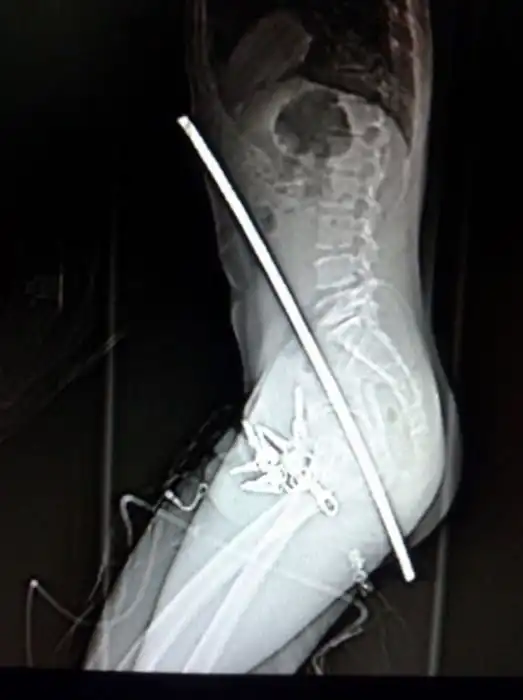

Жуткие рентгеновские снимки

Порой даже не верится, с какими странными и необычными повреждениями в травматологию могут поступить пострадавшие. Всю эпичность профессии врачей травматологии могут с легкостью подтвердить рентгеновские снимки.